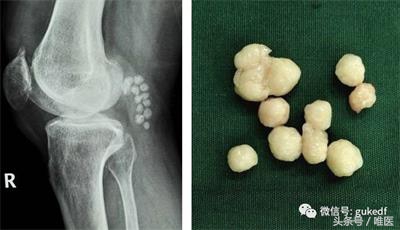

8. 对于关节内软骨剥脱形成游离体,以及半月板撕裂产生卡压、交锁症状的患者可以考虑膝关节镜下清理游离体(图4)和增生的滑膜策划,或镜下微创缝合损伤撕裂的半月板(图5)。前(后)交叉韧带断裂的可行关节镜下的韧带重建手术(图6)。

图4. 膝关节镜清理游离体